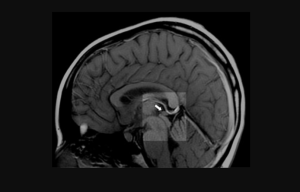

The pineal gland is a pea-sized organ inside the brain that regulates sleep, mood, and hormones.

Zoffi explained that the pathologist found that “the pineal gland was completely destroyed” in mRNA-vaccinated people, causing erratic personality changes.

“And so an Italian pathologist near Venice, he went on a newspaper telling that in all the brains he had investigated, he found the pineal gland was completely destroyed in the people who were vaccinated.”